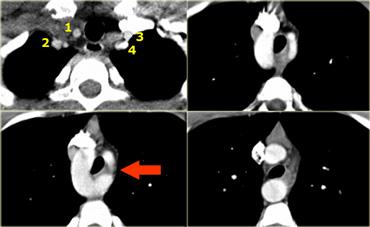

Double Arch with Atretic Segment

Occasionally the double arch can have an atretic segment.

You should not confuse it for a right arch.

The left arch is just very small and there is still a four vessel sign.

On the left a dominant right arch and a small left arch.

The atretic segment is marked by the arrow.

Notice the four vessel sign.

On a posterior view the interruption is nicely demonstrated.

Remember that there is still a ring, so there is still obstruction.

Another case on the left.

Do not call this a right arch.

It still is a double arch and there is a atretic fibrotic segment on the posterior side of the left arch, that completes the ring.

Same patient.

Always look at the airways.

On the recoonstruction the impression on the trachea is better appreciated.